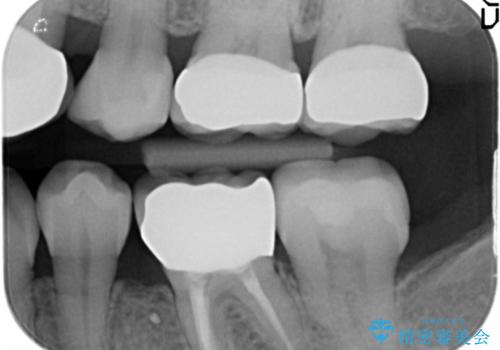

治療途中

左:虫歯を除去したところ。遠心が歯ぐきより深い状態です。中:そのままかぶせようとすると、遠心が歯ぐきが腫れやすい状態です。右:エクストリュージョンをしたことで、遠心の歯ぐきの腫れが収まっていることがわかります。